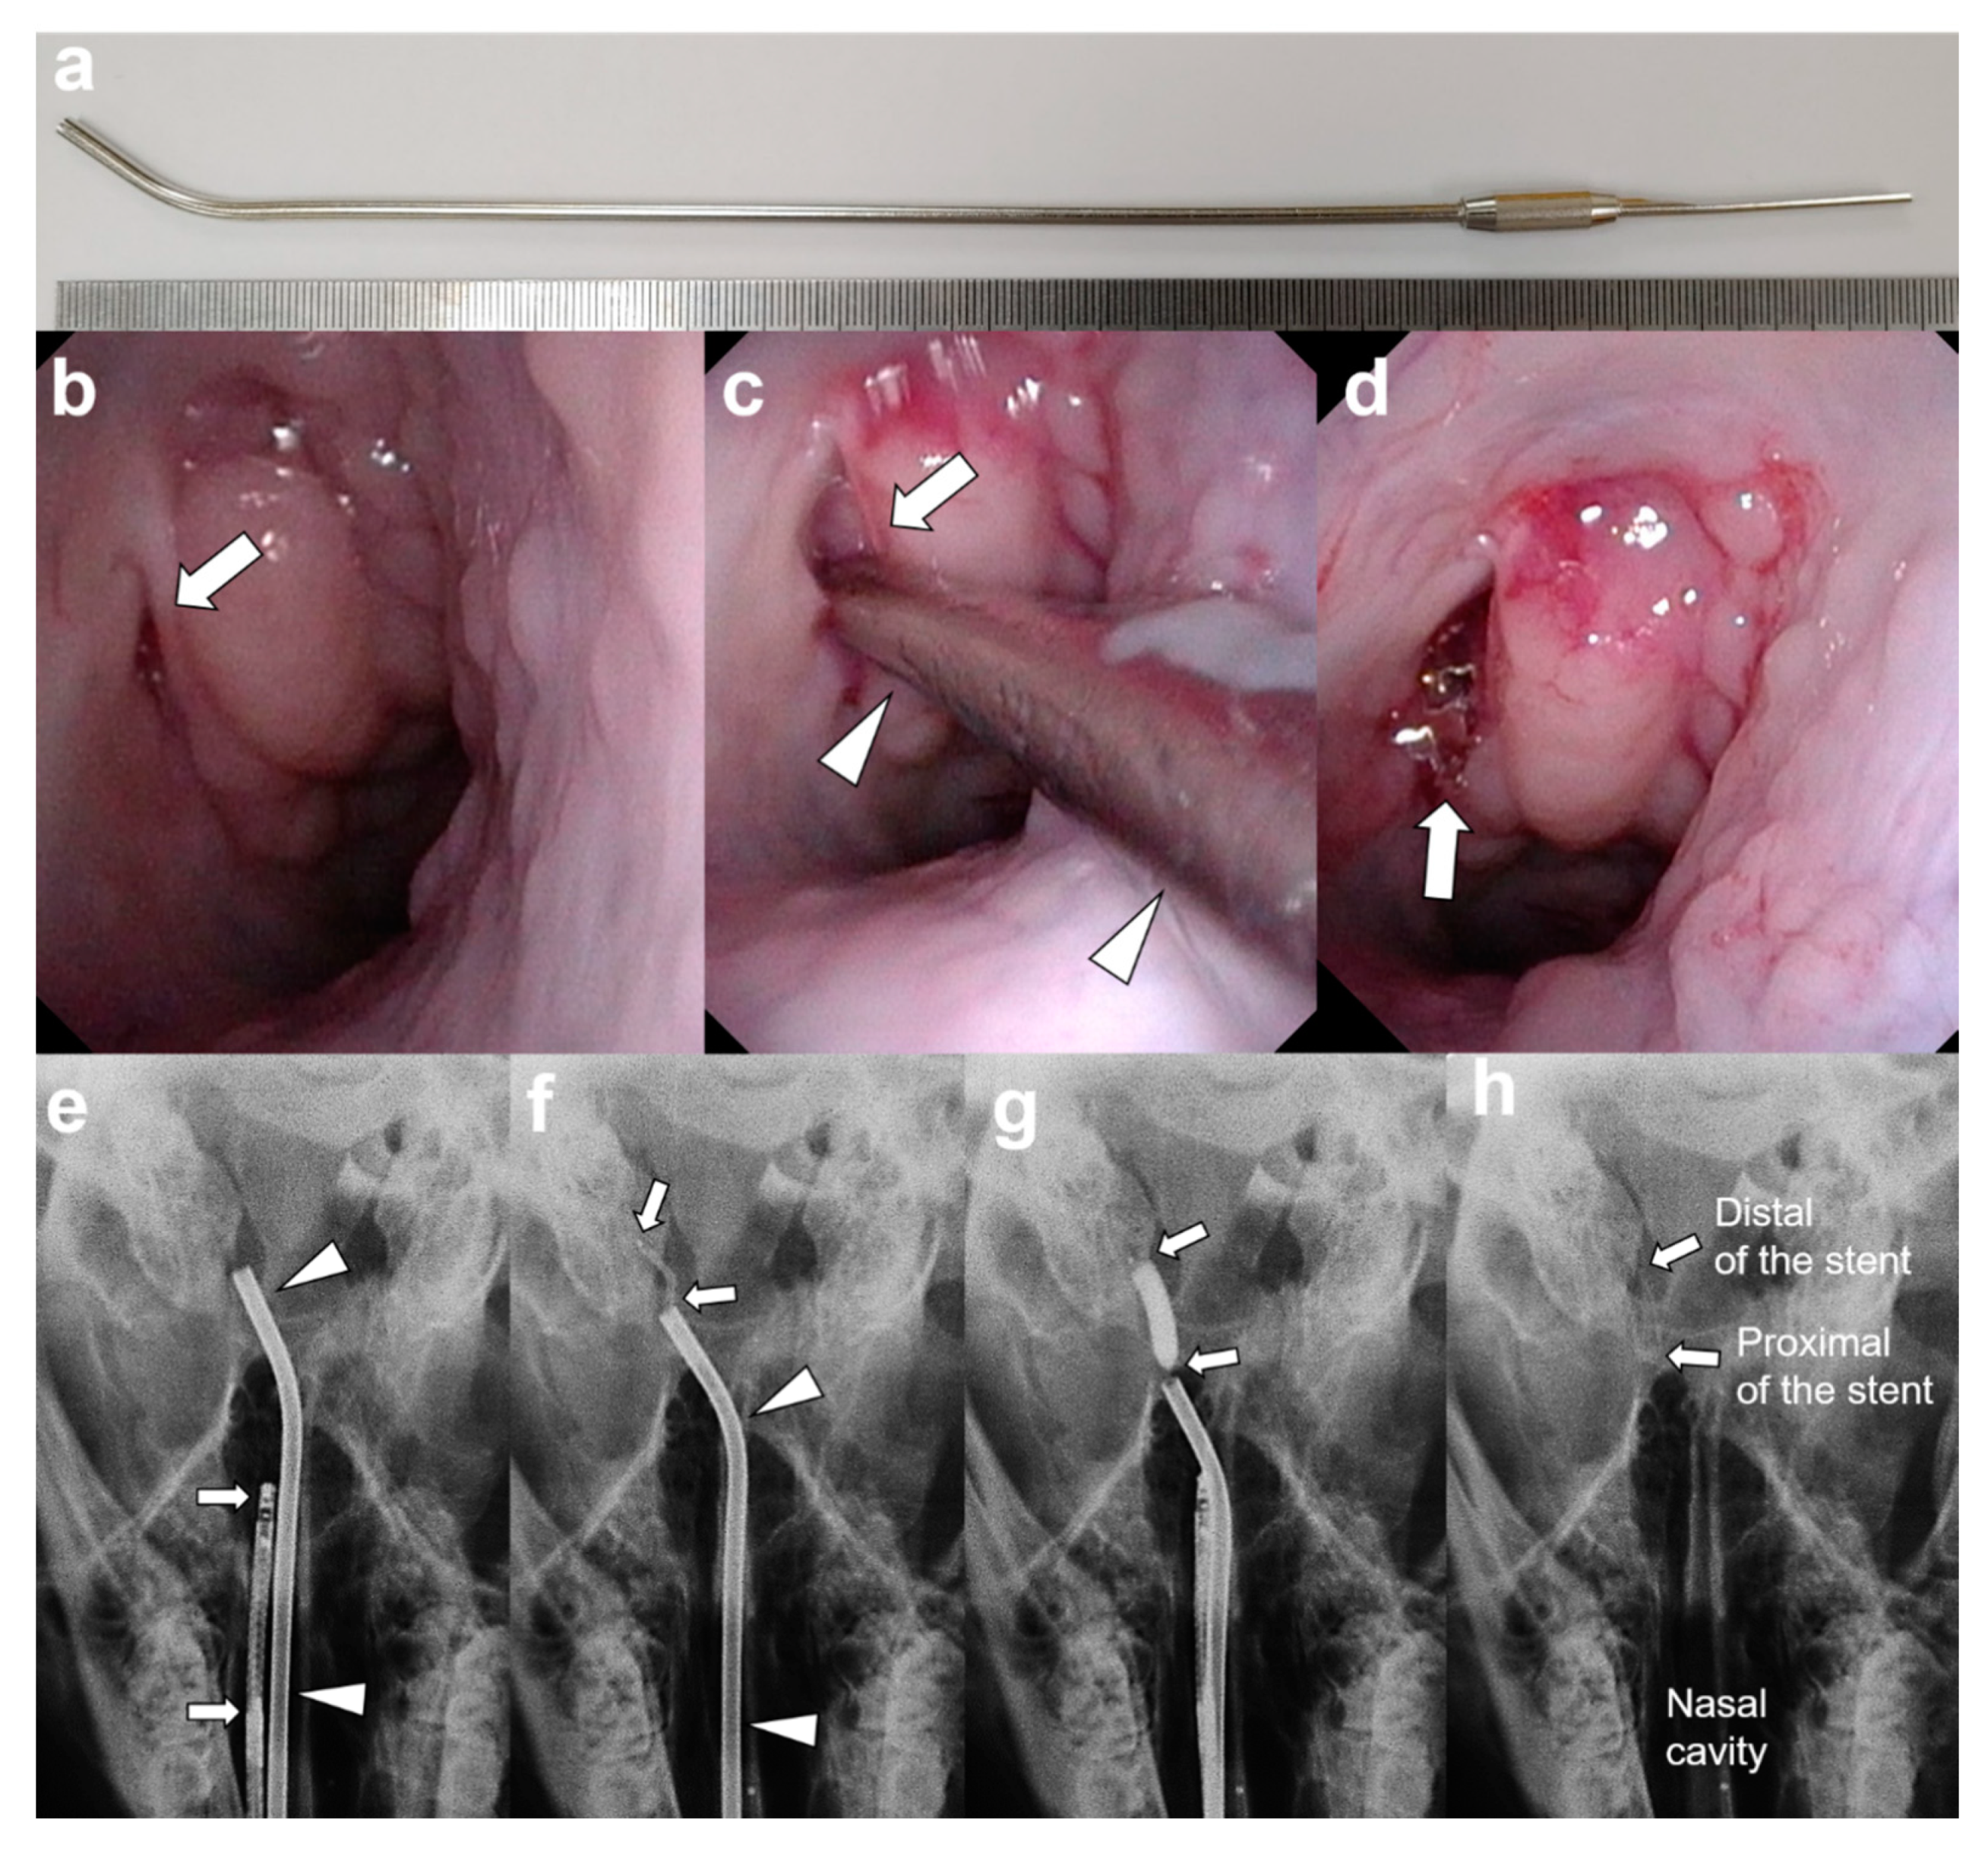

2.2. Metallic Guiding Sheath

2.3. Stent Placement under Endoscopic and Fluoroscopic Guidance